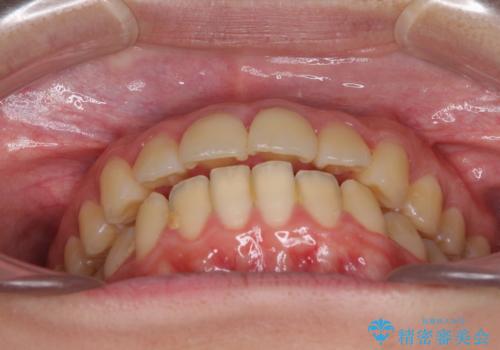

- 口元が出てるのが気になるとのことで来院されました。

歯のがたつきはあまりなかったのですが、口唇が閉じずらく、口元の突出感が確認できました。

口元を下げて口唇を閉じやすくする場合、抜歯矯正をお勧めさせていただくことが多いです。

治療前には必ず患者様とよく相談させていただき、どのようなゴールにするか、それにはどんな治療が必要かをご理解していただいたうえで、治療を開始いたします。